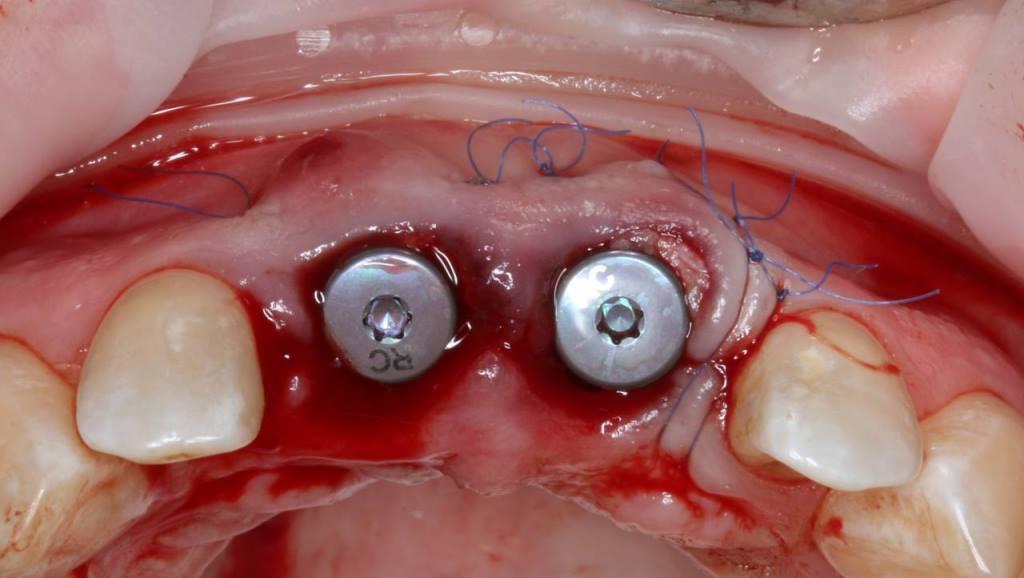

И существует такая методика как IDR - immediately dentoalveolar reconstruction. Суть методики заключается в том, что при дефиците костной ткани мы заполняем пространство костной и мягкой тканями, взятыми с бугра верхней челюсти пациента (за последним зубом). Берется трехслойный трансплантат, и здесь важно до операции по компьютерной томограмме оценить объем донорской зоны. При этом не делается никаких разрезов во фронте. Зубы удаляются очень атравматично, аккуратно, чтобы сохранить все имеющиеся ткани.

Фото 3, 4, 5.

Очень важно во фронтальном отделе корректное параллельное расположение имплантатов во всех трех плоскостях.

Фото 6, 7.